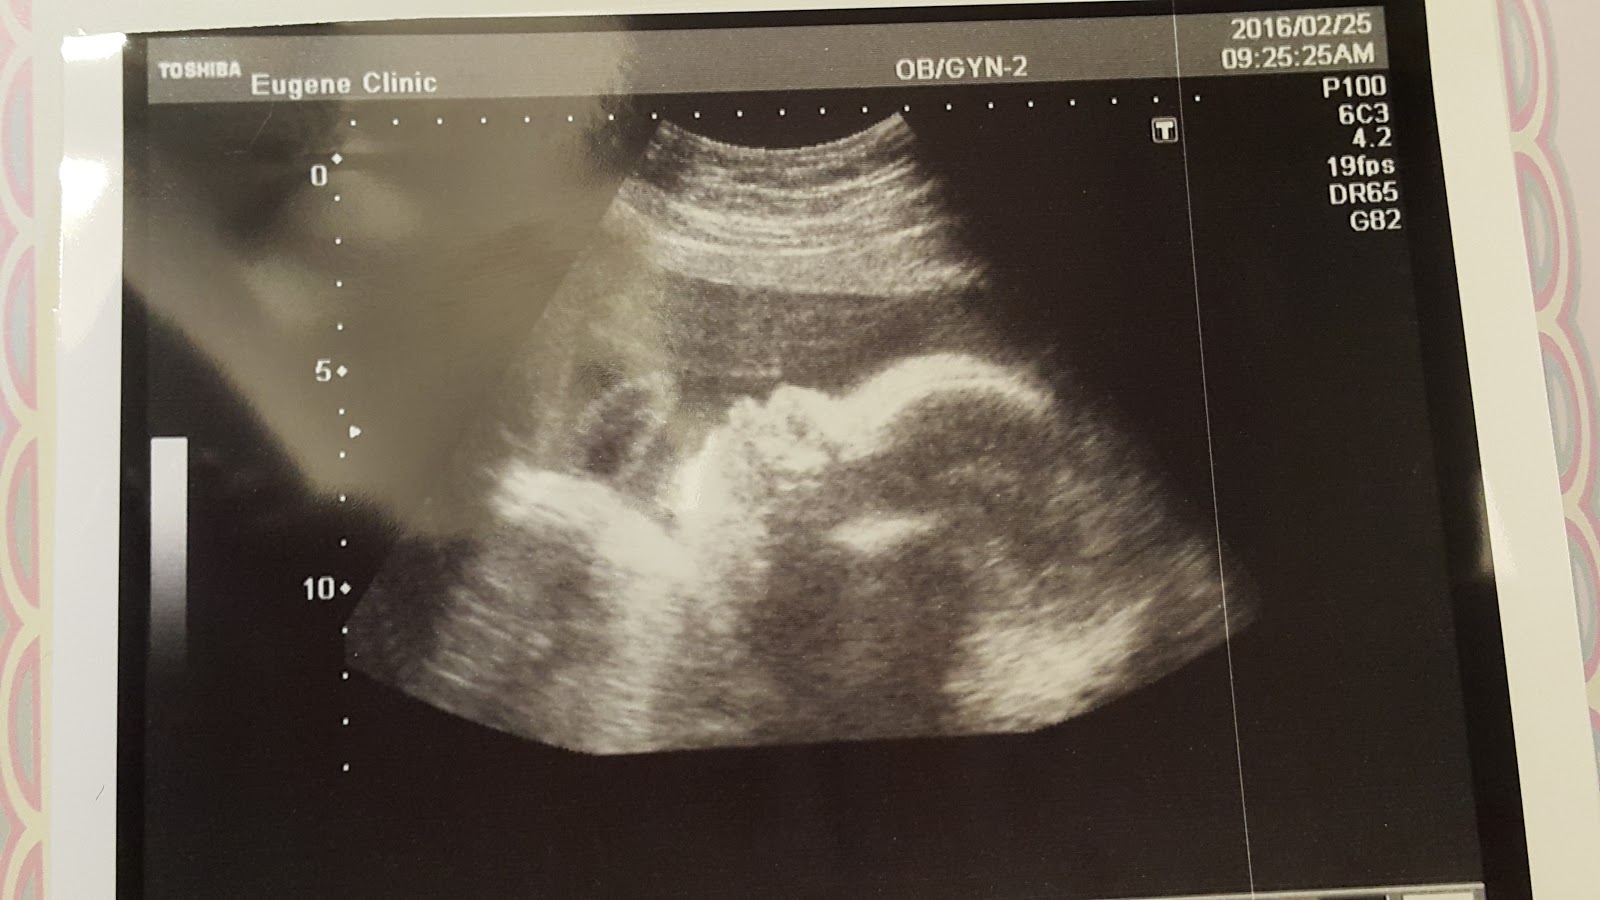

這是Haru的側臉,終於照到側臉了,好開心啊!

不知道為什麼看到baby的側臉超音波照片,有種很peace的感覺

正在檢查的時候,一看到螢幕上的側臉Haru,覺得她好可愛啊~這是我女兒耶~(母愛這時候就爆發會不會太快:P)

醫生說,你看,兩片肉,一定是女生(好羞!是Haru的重要部位啦!)

醫生照超音波看了許多個部位,雖然已經是第二胎,但還是覺得生命很奇妙啊!